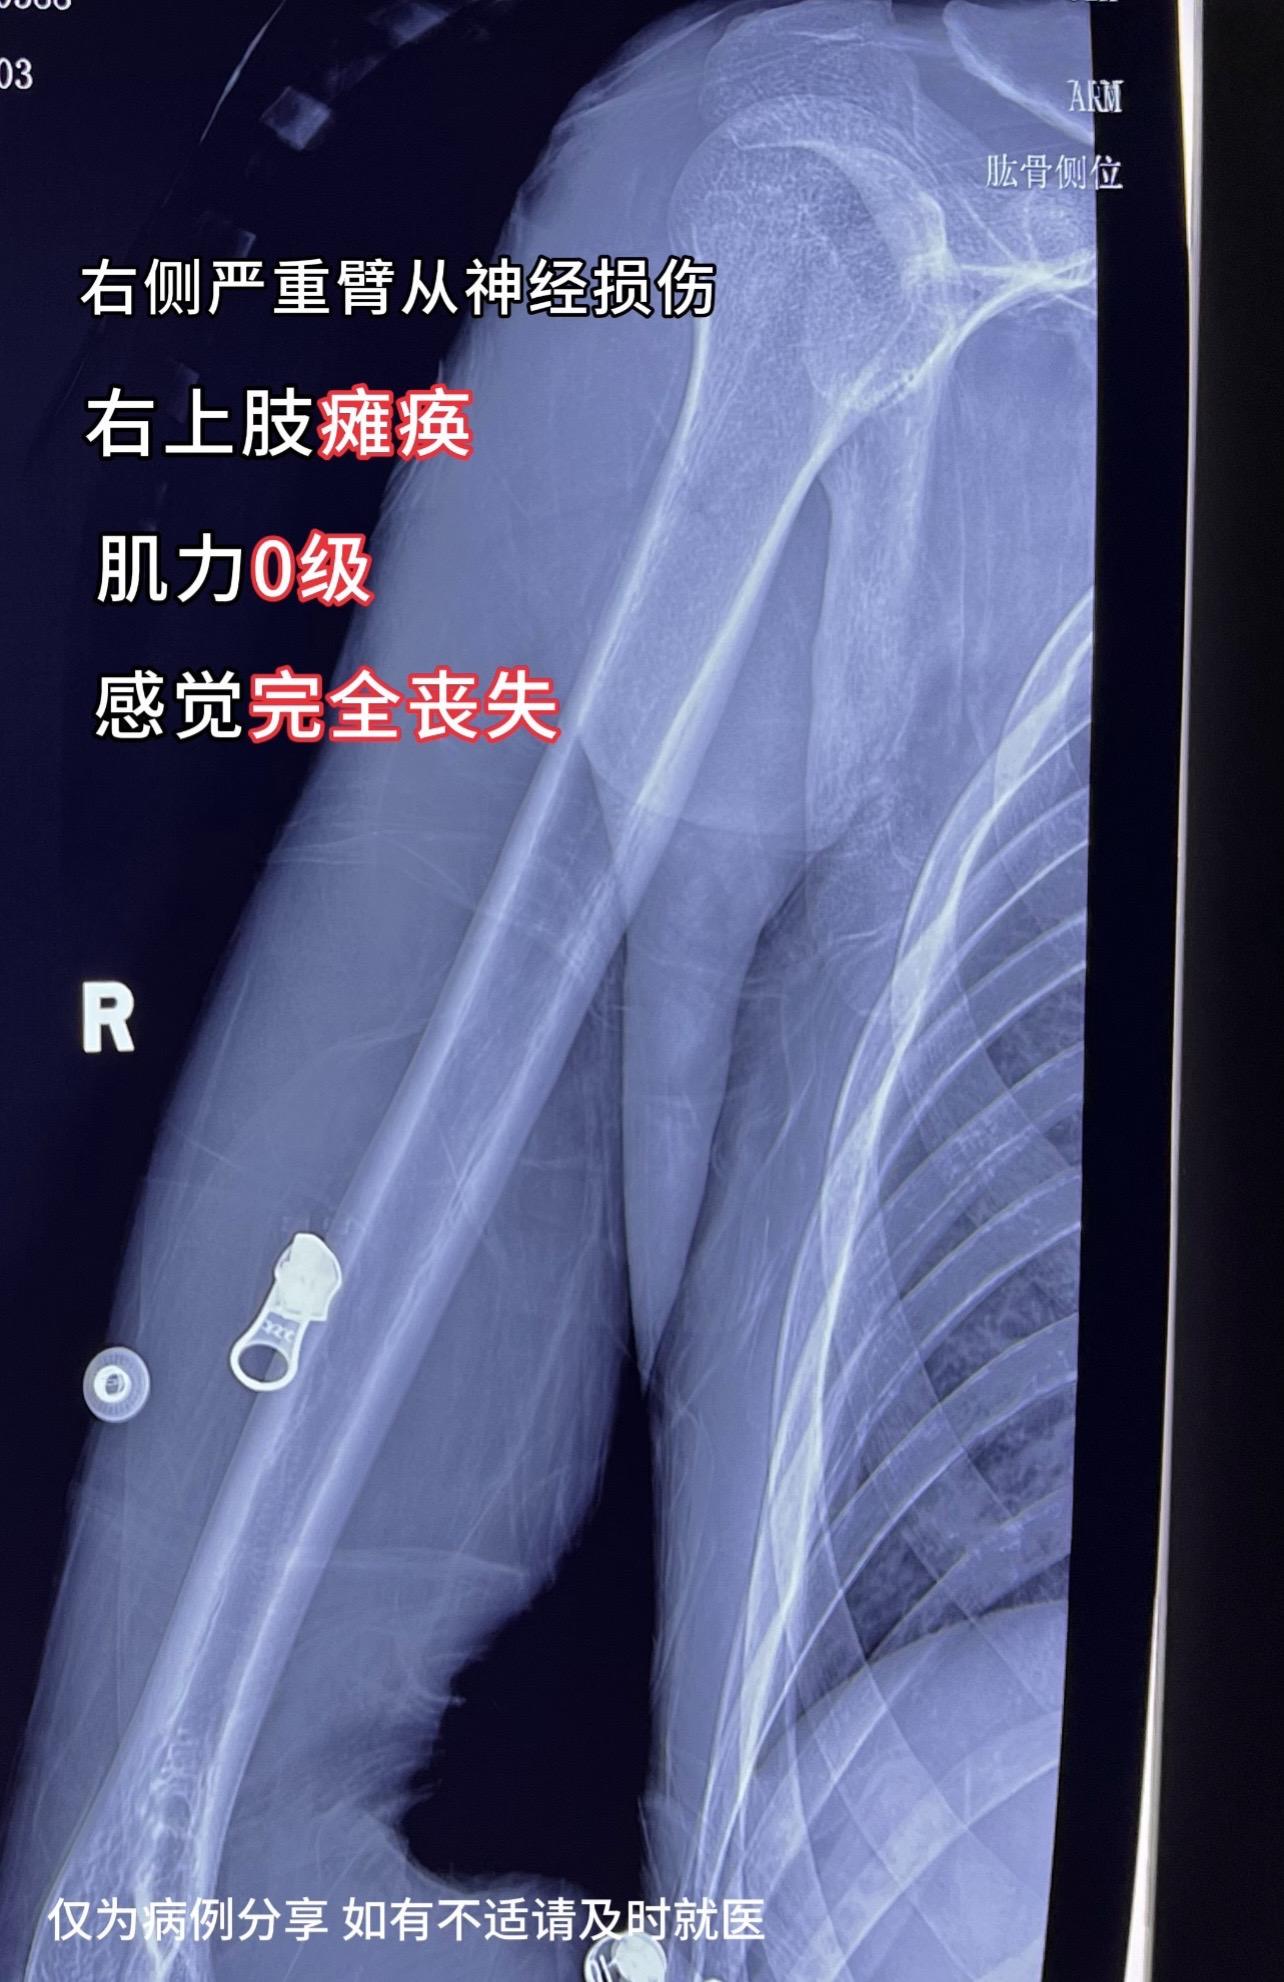

门诊碰到一18岁小伙子,骑摩托车受伤,右侧严重臂从神经损伤,右上肢瘫痪,肌力0级,感觉完全丧失。妈妈,爸爸,奶奶,姑姑…...看着他们痛苦的表情,我心情也十分沉重,花一样的年龄。⚠️骑摩一时爽,痛苦伴终生❗️ 刚哥提醒:骑摩托车肉包铁,速度快,能量高,受伤易导致严重伤致残!